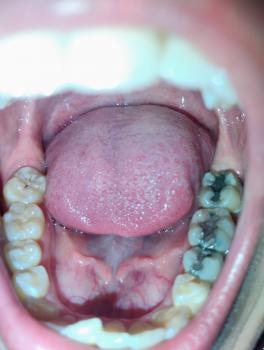

We offer comprehensive dental services tailored to meet individual needs with precision and care:

Dental Check-ups & Oral Consultations

Oral Prophylaxis (Teeth Cleaning)

Dental Fillings (Restorative & Aesthetic)

Root Canal Treatment

Crowns and Bridges

Every patient receives expert advice, clear treatment plans, and personalized care from Dr. Jethro and his professional team.